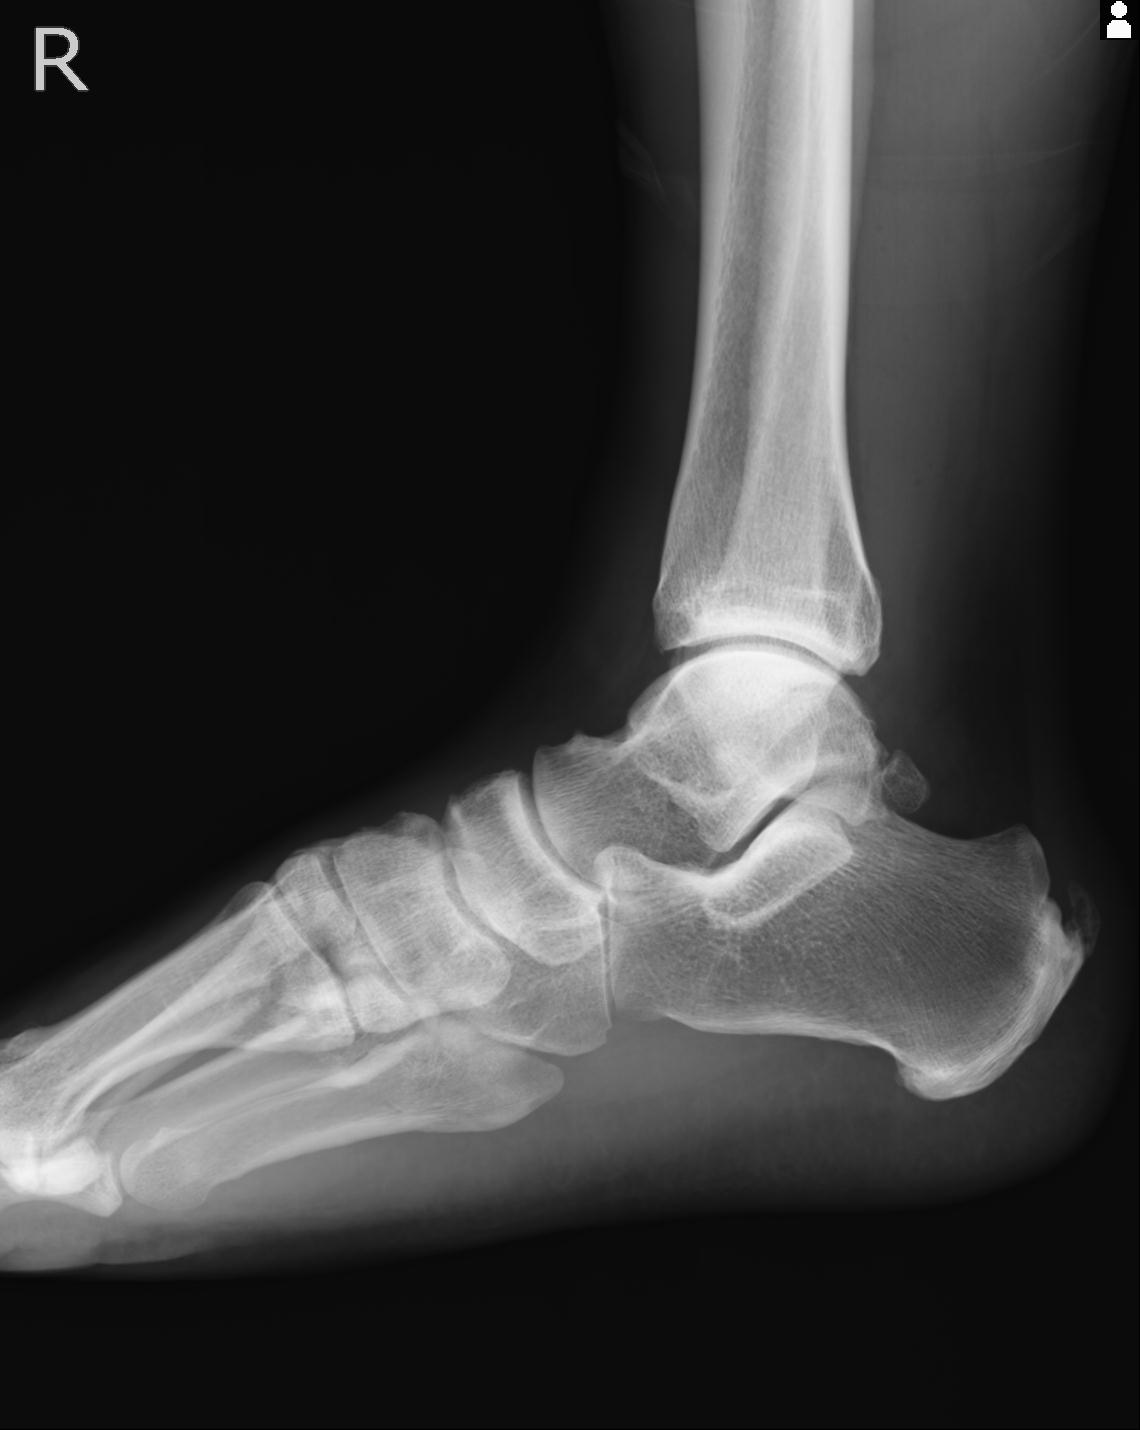

56476 8/28 4R 1/21 2R 左足関節 デジカメ写真 72歳女性 右足関節AS

102755 1/4 2R 1/15 2R 右足関節 68歳女性 右三果脱臼骨折